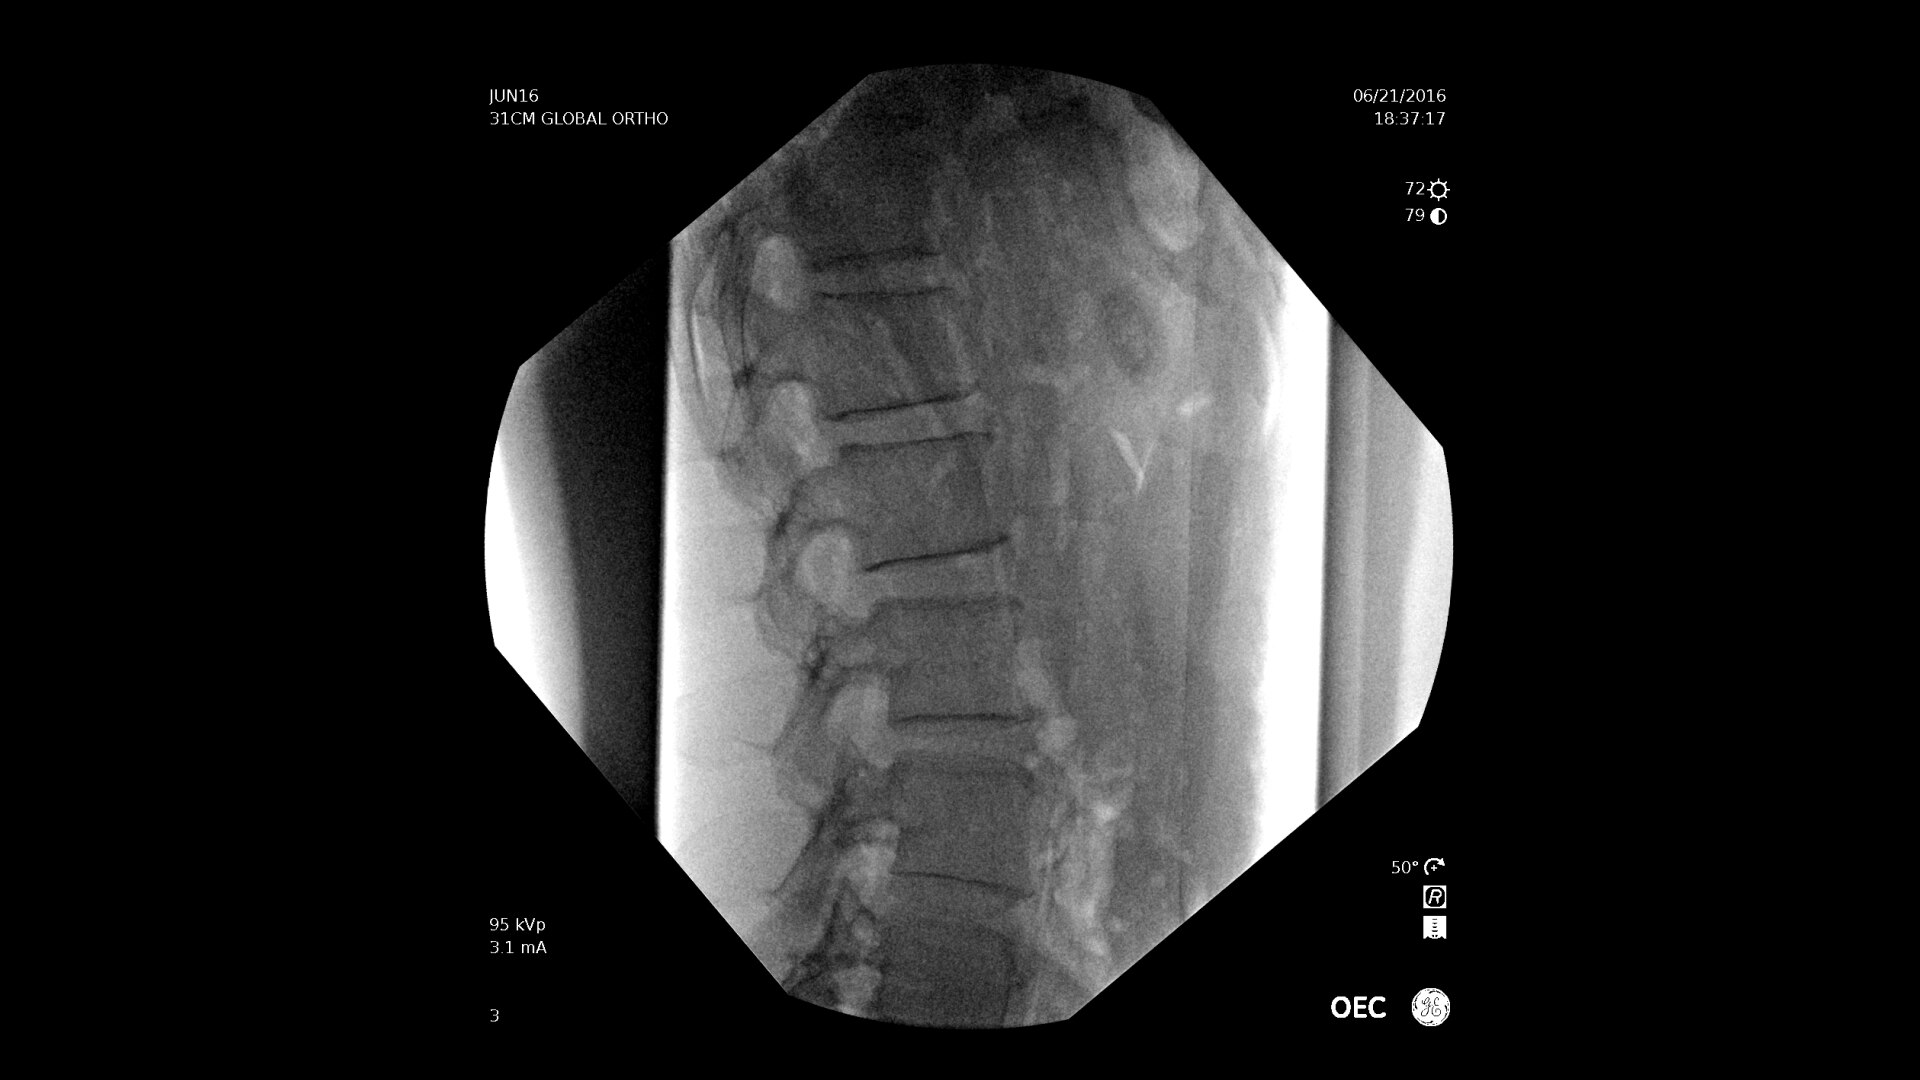

With choice of C-arms to fit a variety of needs, easily obtain challenging spine angles with a 55° overscan, rainbows without moving the base, or a motorized drive.

Experience the benefit of a large field of view up to 22%* larger with the OEC Elite X-ray housing design that enables the detector to get closer to the patient.

Pain management imaging you need

Pain Management procedures require powerful imaging systems.

OEC C-arms perform imaging in a variety of procedures such as:

• Thoracolumbar procedures